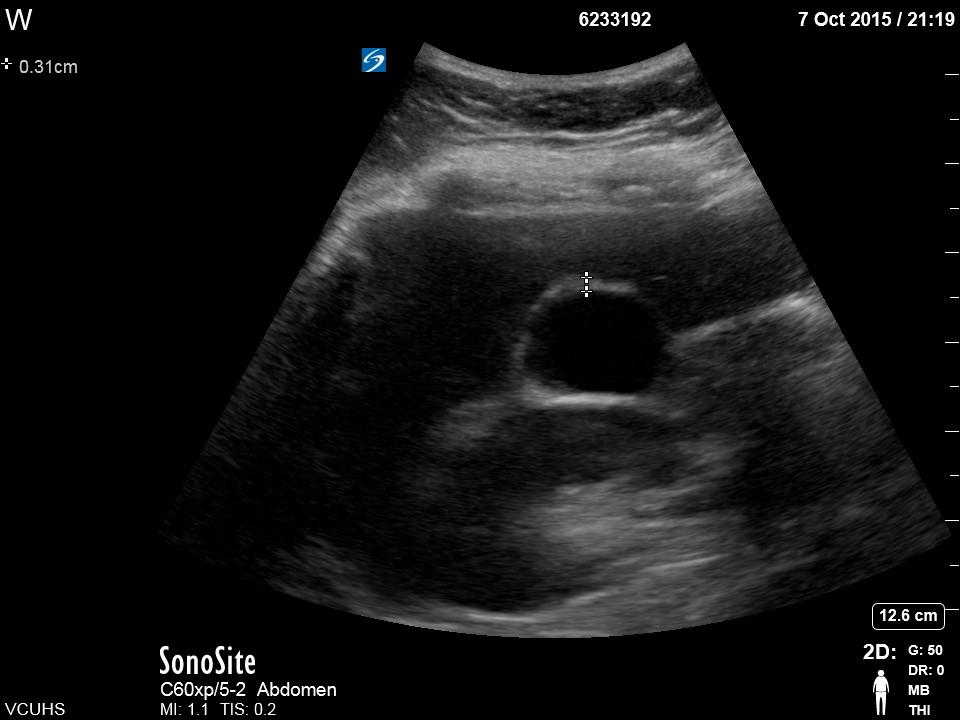

Biliary A. Clip of long axis of GB with portal triad https://vcuultrasound.com/wp-content/uploads/2020/07/0a613-video-8.1-gb-long-axis.mp4 B. Clip of scan through short axis of GB https://vcuultrasound.com/wp-content/uploads/2020/07/c6f26-video-8.2-gb-short-axis.mp4 C. Measurement of CBD with color flow (inner to inner wall) D. Measurement of GB wall in cross section at anterior portion from outer to inner Share this: Share on X (Opens in new window) X Share on Facebook (Opens in new window) Facebook Like Loading...